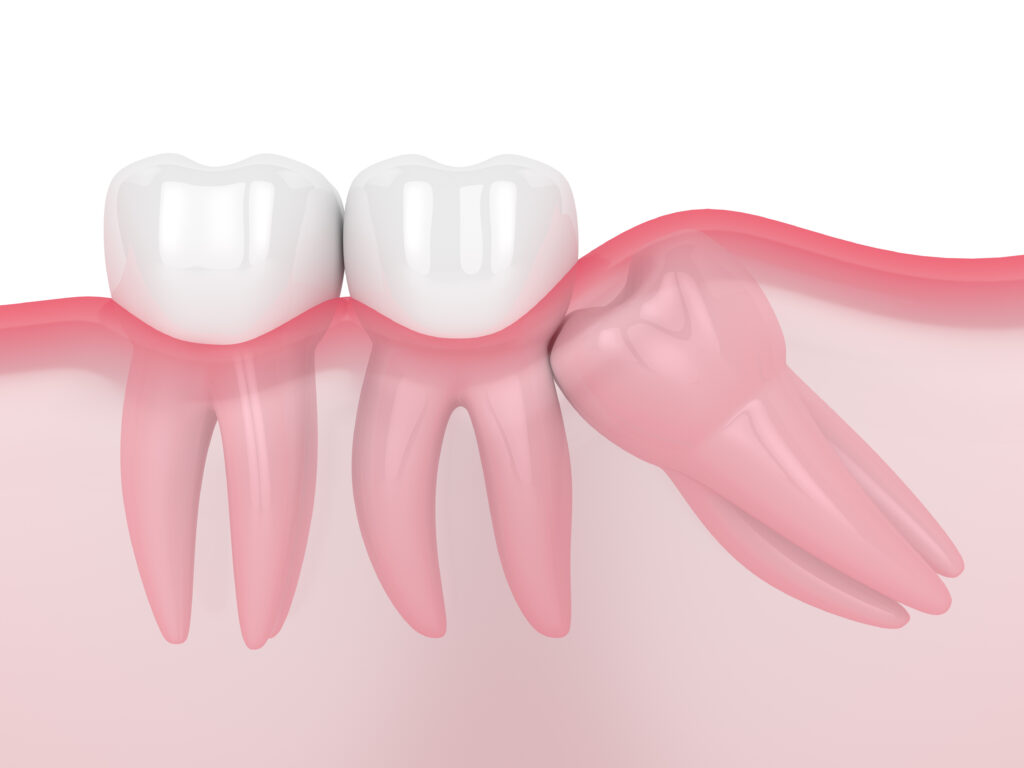

• Wisdom teeth are often unable to fully come out due to the lack of space, known as being impacted, which can lead to pain, swelling, and infection.

• Wisdom teeth can affect the alignment of other teeth by pushing against them.

The procedure to remove a wisdom tooth involves making an incision in the gum to access the tooth. In some complicated cases, the surgeon may need to cut the tooth into small pieces to facilitate removing it. Following the extraction, the surgeon will clean the area, use dissolvable stitches to seal the gums, and help the healing process.